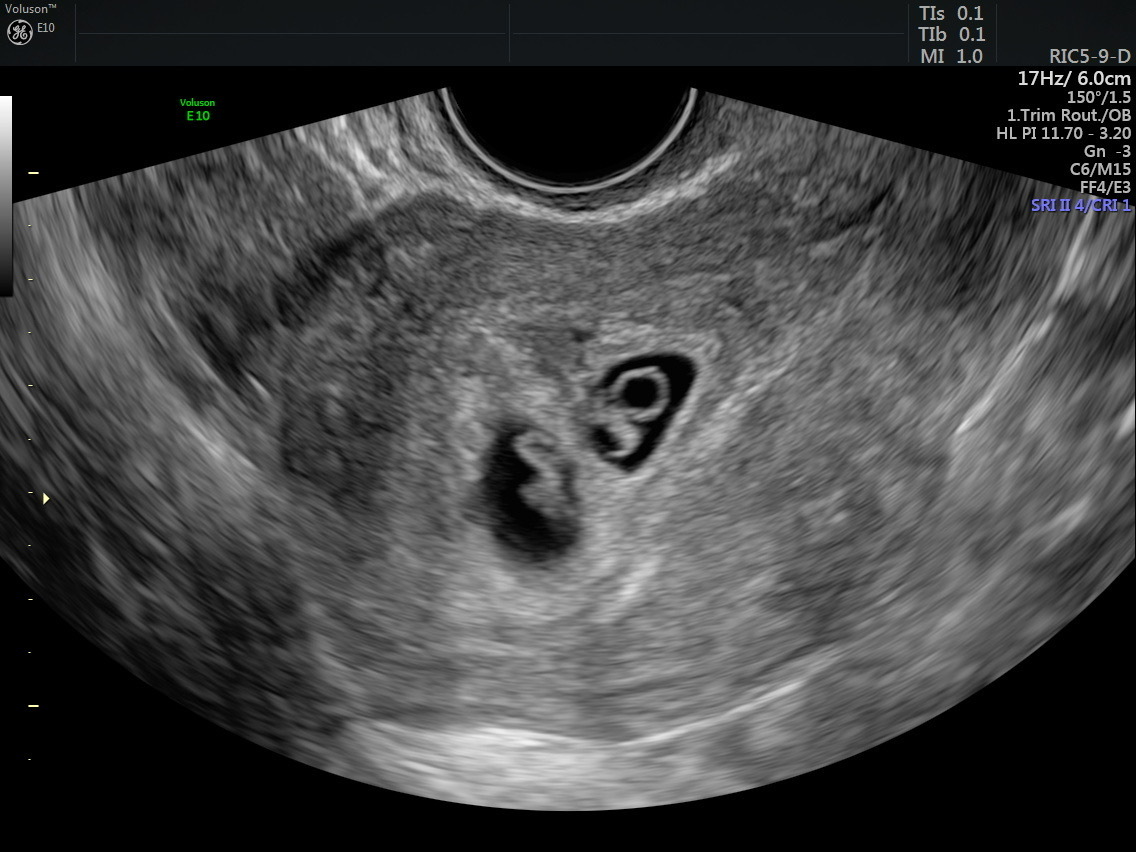

Less than two years ago her husband agreed to look into the process and the couple considered domestic adoption, international adoption and foster-to-adopt. Bowen began researching embryo adoption. These embryos were created through in vitro fertilization. Parents then decide to allow someone else to adopt and implant the extra embryos instead of discarding them.

Bowen had been part of a social media group for those seeking to adopt out embryos. She said it was there that one post caught her eye. Both embryos had preimplantation genetic screening, or PGS. It had a one percent chance of successful implantation. Bowen and her husband chose to implant two of this woman’s embryos.

In November 2021, the Bowens signed an agreement to move forward. Bowen established herself as a patient in a fertility clinic in April of 2022. In August of 2022 the transfer took place.

Her babies were due to be born in May 2023.